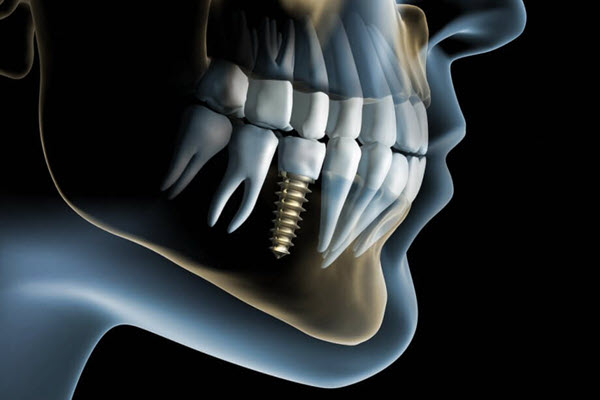

Dental implants are a popular option for patients wanting to recreate the natural look and feel of a missing tooth. The updated service replicates the whole structure of the tooth as part of a cost-effective new approach.

A spokesperson for the clinic states: "Implants are small titanium screws similar in size to a tooth root. They are placed into the jaw bone in placement of a missing tooth or teeth. Implants are then covered with a crown which is made of ceramic or porcelain materials to simulate a tooth."